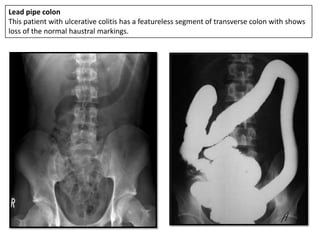

Lead pipe colon

This patient with ulcerative colitis has a featureless segment of transverse colon with shows

loss of the normal haustral markings.